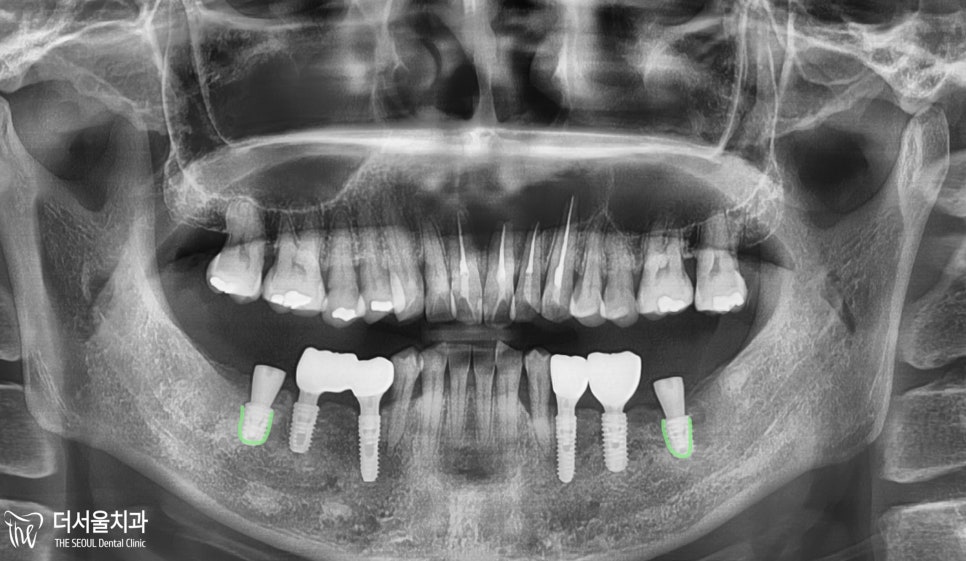

파노라마 엑스레이를 촬영했는데

아래쪽 어금니를 상실한 것을 볼 수 있었으며

위쪽 어금니와 맞물리지 못하므로

음식을 저작하는 기능이 떨어질 수밖에 없었습니다.

#37,47번 부위에

컴퓨터 분석 임플란트 를 진행한 모습입니다.

잇몸 절개 없이

계획한 부위에 픽스쳐를 심었으며

그 위에 힐링 어버트먼트를 체결하게 되었습니다.